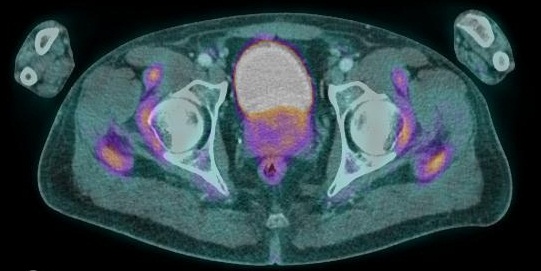

PPR ( Bursite des racines des membres et inter épineuse lombaire) associée à une vascularite de Horton ( hypermétabolisme des parois des artères vertébrales )

Magnifique PPR avec des bursites classiques (gléno-humérales, coxo-fémorales, ischiatiques, trochantériennes, interépineuses lombaires et cervicales) et des localisations plus rares : ilio-pectinées, petit trochanters, interapophysaires lombaire… Et une localisation que je n’avais jamais vu : base des épines scapulaires (si quelqu’un connaît le nom de cette bourse je suis preneur).

Hypermétabolisme de la portion horizontale des artères vertébrales (et des hypermétabolisme focaux sur l’iliaque interne et l’origine du TABC), suspect de maladie de Horton. BAT positive par la suite.